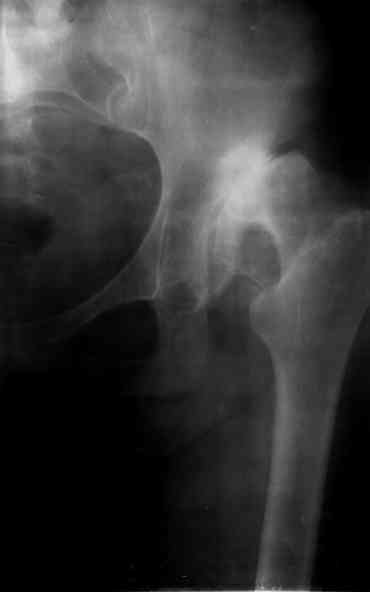

Ув. коллеги, женщина, 37 лет, имеет диспластический коксартроз. Сомневается в положительном результате от эндопротезирования, но хочет оперироваться. Что порекомендуете? С ув. Sergey A. Melashenko ул. Кирова 88-А, г. Приморск, Запорожская обл., 72100, Украина

Оперироваться. Альтернативы нет. Надо делать обе ноги, поочередно с реконструкцией крыш для последующей удобной ревизии. Ножки бесцементные.

Остальное дело техники. С ув. А Рыков. Хабаровск. Мы бы взялись.

Сергей. Операция первичного эндопротезирования предусматривает у данной больной (я бы сделал так) - 1. Доступ с хорошим обзором впадины (или задний

или с пересечением б.вертела) - затем установку тазового компонента с одномоментной пластикой крыши вертлужной впадины из утилизируемой головки

(если получится бесцементная чаша - это лучше, но не факт - вероятно будет моделирующее кольцо с цементируемой чашей - внимание к "версии" чаши) -

затем классическая бесцементная ножка. Справа будет попроще. Слева рассчет после установки правого сустава. Может потребоваться двухэтапное

протезирование. При отсутствии проблем с финансировании - отправьта в Харьков - Киев - Донецк. С уважением. А Рыков.

1. при таком анатомическом варианте корригирующие остеотомии явно проигрывают тотальному эндопротезированию.

2. первым этапом оперируем сторону с преобладающим болевым.

3. справа может быть будет достаточно структурного аутотрансплантата, но вариант с кольцом надо иметь в виду; слева использовал бы армирующую конструкцию (плохая надацетабулярная кость - проблемное приживление трансплантата).

4. вероятность осложнений выше, чем в банальной ситуации, правильно дама беспокоится, лучше делать операцию там, где это на потоке. Если ближе не найдется, присылайте.